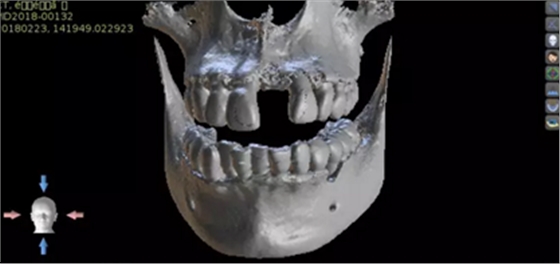

1.術(shù)前CT

2.術(shù)前植體設(shè)計(jì)

術(shù)后CT